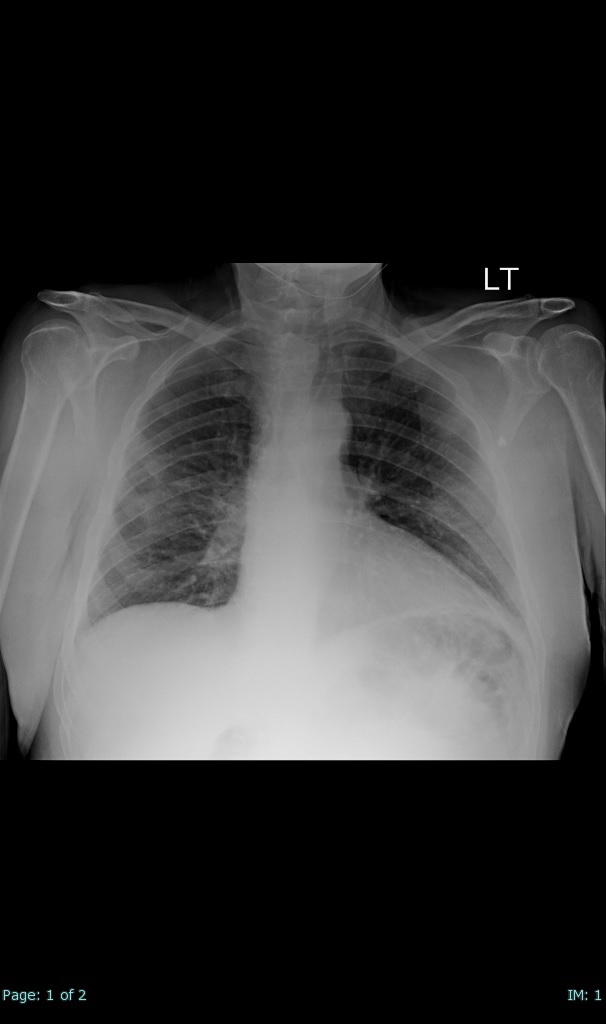

- 66% had some + CXR finding I could correlate to a CT finding

- 66% had documented exposure, rest I couldn't find either way